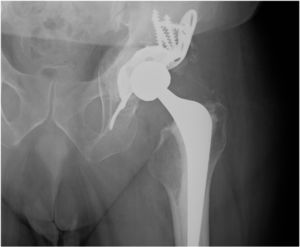

Radiological evaluation showed fracture healing in all patients, and we observed no complications such as screw breakage, implant displacement or mispositioning of the acetabular component. All patients had Gie’s grade 3 osseointegration (Fig. 3), 3 patients had grade I heterotopic calcifications according to Brooker’s classification, one grade II and one grade III, which did not result in functional limitation in any of the cases.

On admission, the fracture was reduced under sedation, lateralising the root of the thigh by manipulation in the case of central protrusion of the femoral head and supracondylar femoral skeletal traction between 5 kg and 7 kg was maintained until surgery. Prophylaxis for thromboembolic disease was 40 mg of subcutaneous low molecular weight heparin every 24 h, and 3 doses/1 g of cefazolin/every 8 h were used for infection, as we use for elective hip arthroplasty, starting 30 min before the prosthetic surgery. Three surgeons experienced in both hip revision surgery and pelvic fractures operated on all the patients, under general anaesthesia in each case. The surgical technique was similar in all cases, following the same protocol using a direct lateral Hardinge Bauer approach, osteotomy of the femoral neck without prior dislocation of the femoral head so as not to increase fracture displacement, removal of the femoral head using a corkscrew, reduction of the fracture with direct visualisation of the cup by means of instrumented manipulation of fragments as far as possible without seeking anatomical reduction, careful resection of the acetabular cartilage using an acetabular reamer, filling of the acetabular floor with crushed and compacted autologous graft of the femoral head, implantation of a titanium BS cage screwed on the roof of the acetabulum and iliac bone and ischial anchorage, and cemented "all-poly" cup type Müller® (Zimmer®, Winterthur, Switzerland) on the cage. Cemented Exeter® (Stryker Inc®, Newbury, UK) femoral stem in 8 patients and cementless Sl-Plus® (Smith & Nephew Orthopaedics® AG, Switzerland) in 5 depending on their bone quality. We used a 32 mm head and polyethylene metal torque in all cases.